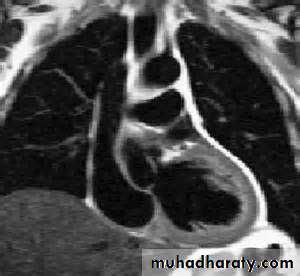

Magnetic resonance imagingMagnetic resonance imaging (MRI) requires no ionising radiation and can be used to generate cross-sectional images of the heart, lungs and mediastinal structures